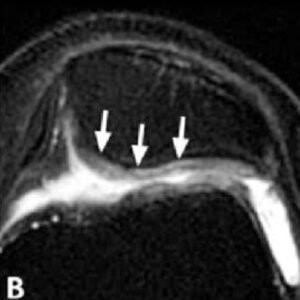

Chondromalacia patellae grades II–IV in various patients.

(B) Axial FSE PD FS MR image of chondromalacia patellae grade III in a 51-year-old female. There is full thickness focal signal intensity change, contour irregularity and thinning of the cartilage (arrows).